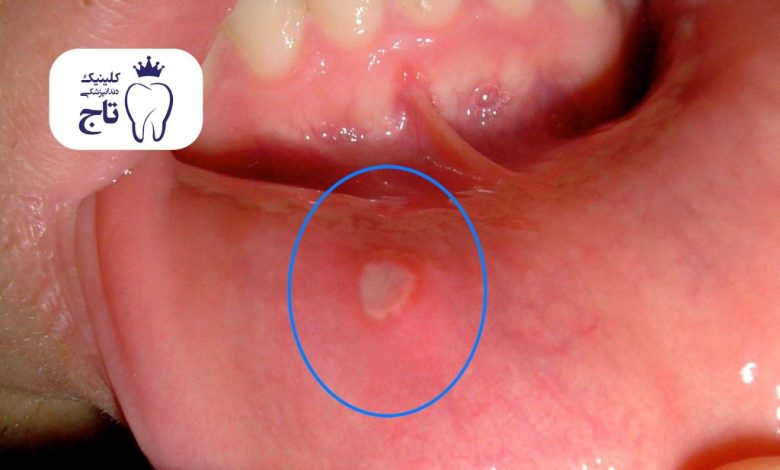

آفت دهان یکی از شایعترین انواع جوش داخل دهان است که به شکل لکههای گرد یا بیضی ظاهر میشود. این جوشها معمولاً مرکزی سفید یا زرد دارند و اطراف آنها قرمز و ملتهب است. آفتها اغلب روی سطح داخلی گونه، لبها یا کف دهان دیده میشوند و به طور ناگهانی ظاهر میشوند.

یکی از ویژگیهای آفتها، اندازه کوچک اما دردناک بودن آنها است. این ضایعات باعث ایجاد ناراحتی در هنگام غذا خوردن یا صحبتکردن میشوند. آفتها معمولاً تک لکهای هستند، اما در برخی افراد چندتایی نیز بروز میکنند. ازآنجاییکه آفتها محدود به بافت نرم دهان میشوند، در عکسبرداری دندان یا معاینه استخوانی نشانهای از آنها دیده نمیشود. این نوع جوش دهانی اغلب موقت است؛ اما ظاهر آن برای بسیاری از بیماران نگرانکننده است، به صورت ویژه آفت دهان کودکان برای مادران بسیار نگران کننده و عذاب آور است.